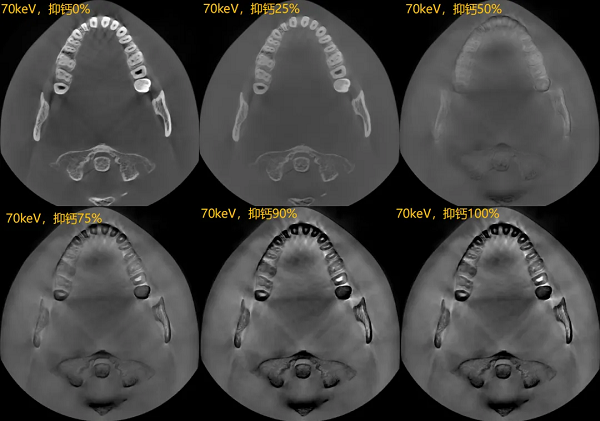

去钙图:双能技术可以有效识别骨质中的钙成分,并特异性地对钙成分进行抑制,而且这种抑制可以进行不同程度的调节;对于受骨钙成分影响较大的骨髓显影,有着优异的临床效果。

有效原子序数图:双能技术可以在双能量成像过程中,将口腔内所有组织的成分进行分离,按照这些物质的原子序数大小进行特异性渲染;对于隐裂/口腔癌等传统影像无法分辨的临床问题,有着特异性的鉴别能力。